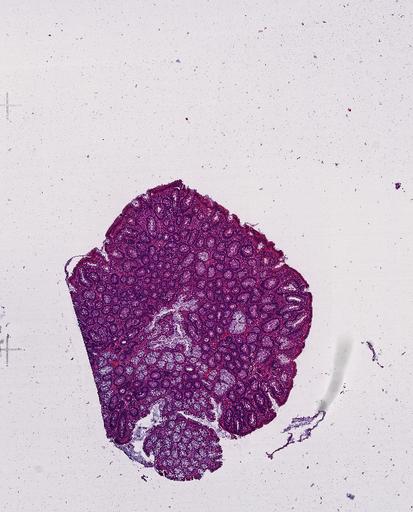

High‑resolution three‑dimensional (3D) tissue atlases promise to redefine how we study cellular architecture‑function relationships in human tissues. Large-scale consortia such as the Human Bimolecular Atlas Program (HuBMAP) systematically build detailed 3D organ maps by profiling serial tissue sections with single-cell spatial technologies. However, an accurate and efficient reconstruction method that can handle atlas-scale datasets remains elusive. We introduce Space-map, an open-source method that integrates single‑cell coordinates with optional histological image features to assemble serial sections into 3D models. Space‑map combines multi‑scale feature matching with large‑deformation diffeomorphic metric mapping, delivering global reconstructions while preserving local micro‑anatomy. To demonstrate the capability of Space-map, we generated a serially sectioned spatial transcriptomics (Xenium, ~2.9M cells) dataset and a spatial proteomics dataset (CODEX, ~2.4M cells). Applying Space-map to these single-cell spatial maps, we built three 3D models for both diseased (colon polyp) and reference colon tissues. These high-resolution 3D models showcase the intricate structure of the human colon across different states. Space-map is fast and highly efficient. We demonstrated its performance and accuracy using in‑house and public datasets. The result shows that Space‑map is 10 times faster and ~2‑fold more accurate than PASTE and STalign, making 3D atlas reconstruction more accessible. Our study provides a new robust and user-friendly software available at https://github.com/a12910/spacemap that can be easily applied for constructing molecular 3D tissue maps of human organs at single-cell resolution.